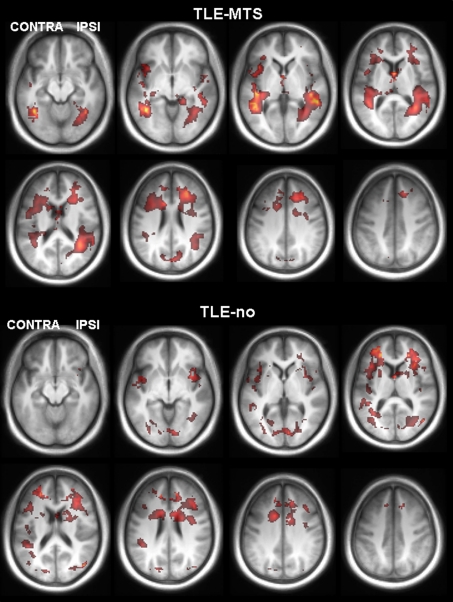

Figure 2 displays the results of the group analysis. NAA/(Cr+Cho) abnormalities in TLE-MTS had a bilateral temporo-occipital distribution. Additional prominent abnormalities were present in both frontal lobes. NAA/(Cr+Cho) abnormalities in TLE-no were more diffuse and less well-defined and were most prominent in the temporo-insular and bilateral frontal regions. The direct comparisons between TLE-MTS and TLE-no showed no significant differences at the chosen significance threshold.

Fig. 2.

Regions with significant decreased NAA/(Cr+Cho) in TLE-MTS compared to controls (upper two panels) and TLE-no compared to controls (lower two panels). Abnormalities in TLE-MTS were most prominent in the bilateral temporal lobes but extended also into posterior occipital and frontal regions. Abnormalities in TLE-no were more diffuse, less distinct and preferentially in bilateral frontal, temporal-insular regions. Similarly, as in the single subject analysis, there was no clear predominance of the NAA/(Cr+Cho) reductions in the ipsilateral hemisphere in either group